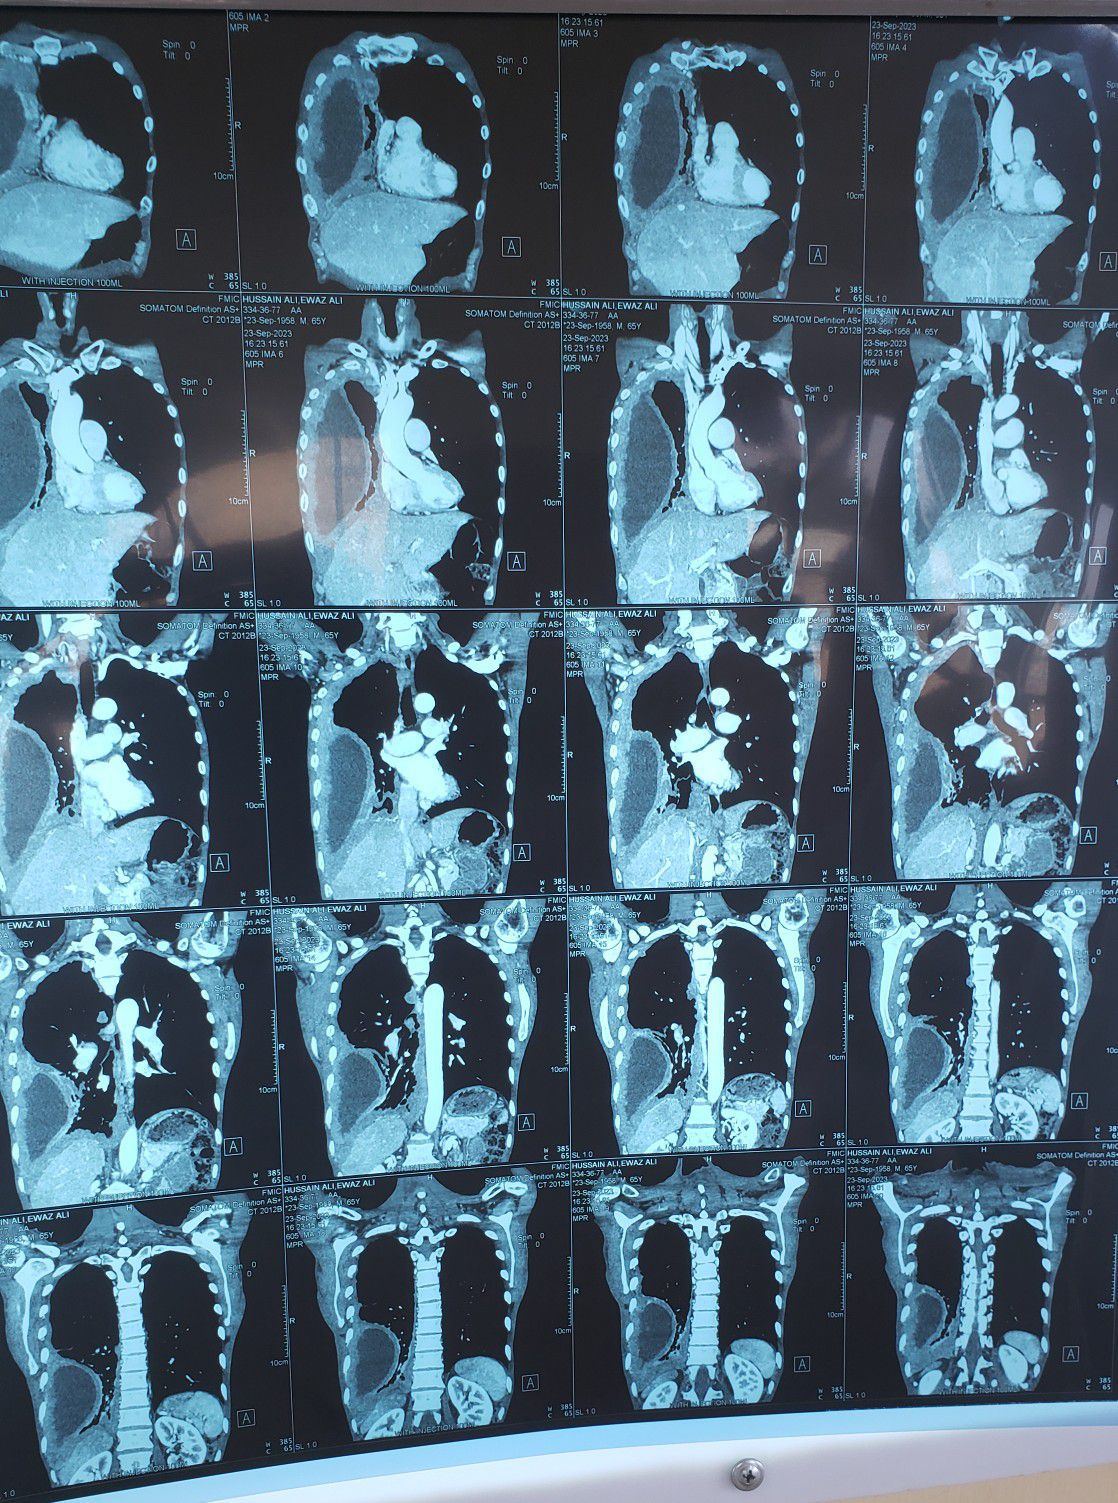

Mesothelioma

Medical

Pathology

Antomy